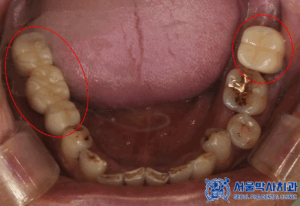

확인해보니,

치아가 상실된 부위도 많고

남아있는 치아들이

흔들리는 상황이였는데요.

왼쪽 아래 사랑니를 포함한 큰어금니는

맞닿는 위 치아가 없어

정출되어 있는 상황이였고

식립한 임플란트가 잘 치유되어

보철 작업을 시작하였습니다.

보철 작업은 디지털 장비를 활용해

정밀하게 진행되었으며,

환자분의 자연치아와

유사한 기능과 형태를

복원할 수 있도록 최선을 다했습니다.

마무리 후 사진입니다.